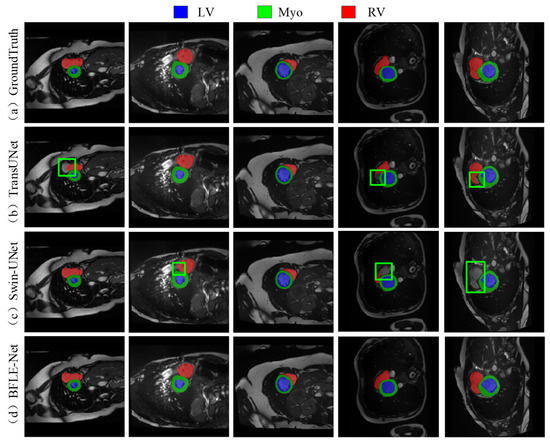

As shown in Figure 7, the existing methods also show obvious limitations in the right ventricle segmentation task in the ACDC dataset. Both TransUNet and Swin-UNet struggle with missing the right ventricle structure. By adopting a dynamic feature calibration mechanism, the method in this study completely preserves the fine anatomical structural features of the right ventricle and significantly optimizes boundary continuity.

Figure 7. Qualitative analysis results on the ACDC dataset. Note: The green box in the figure indicates the location where the effect of segmentation is insufficient.